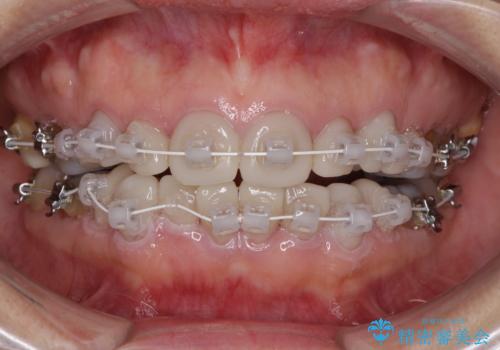

- 矯正装置

- 審美装置

- 治療期間

- 1年3ヶ月

- 治療回数

- 10-30回